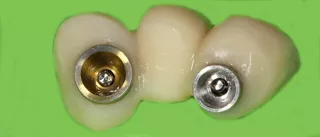

15. Same emergence profile between resin and zirconia bridges. Enameling only on the vestibular surface. The zirconia was carefully polished where it contacted soft tissue.

16a-b. Final situation after inserting bridges to 15 Ncm, cementing the crown to tooth 15, and gluing the veneers to teeth 11 and 21.